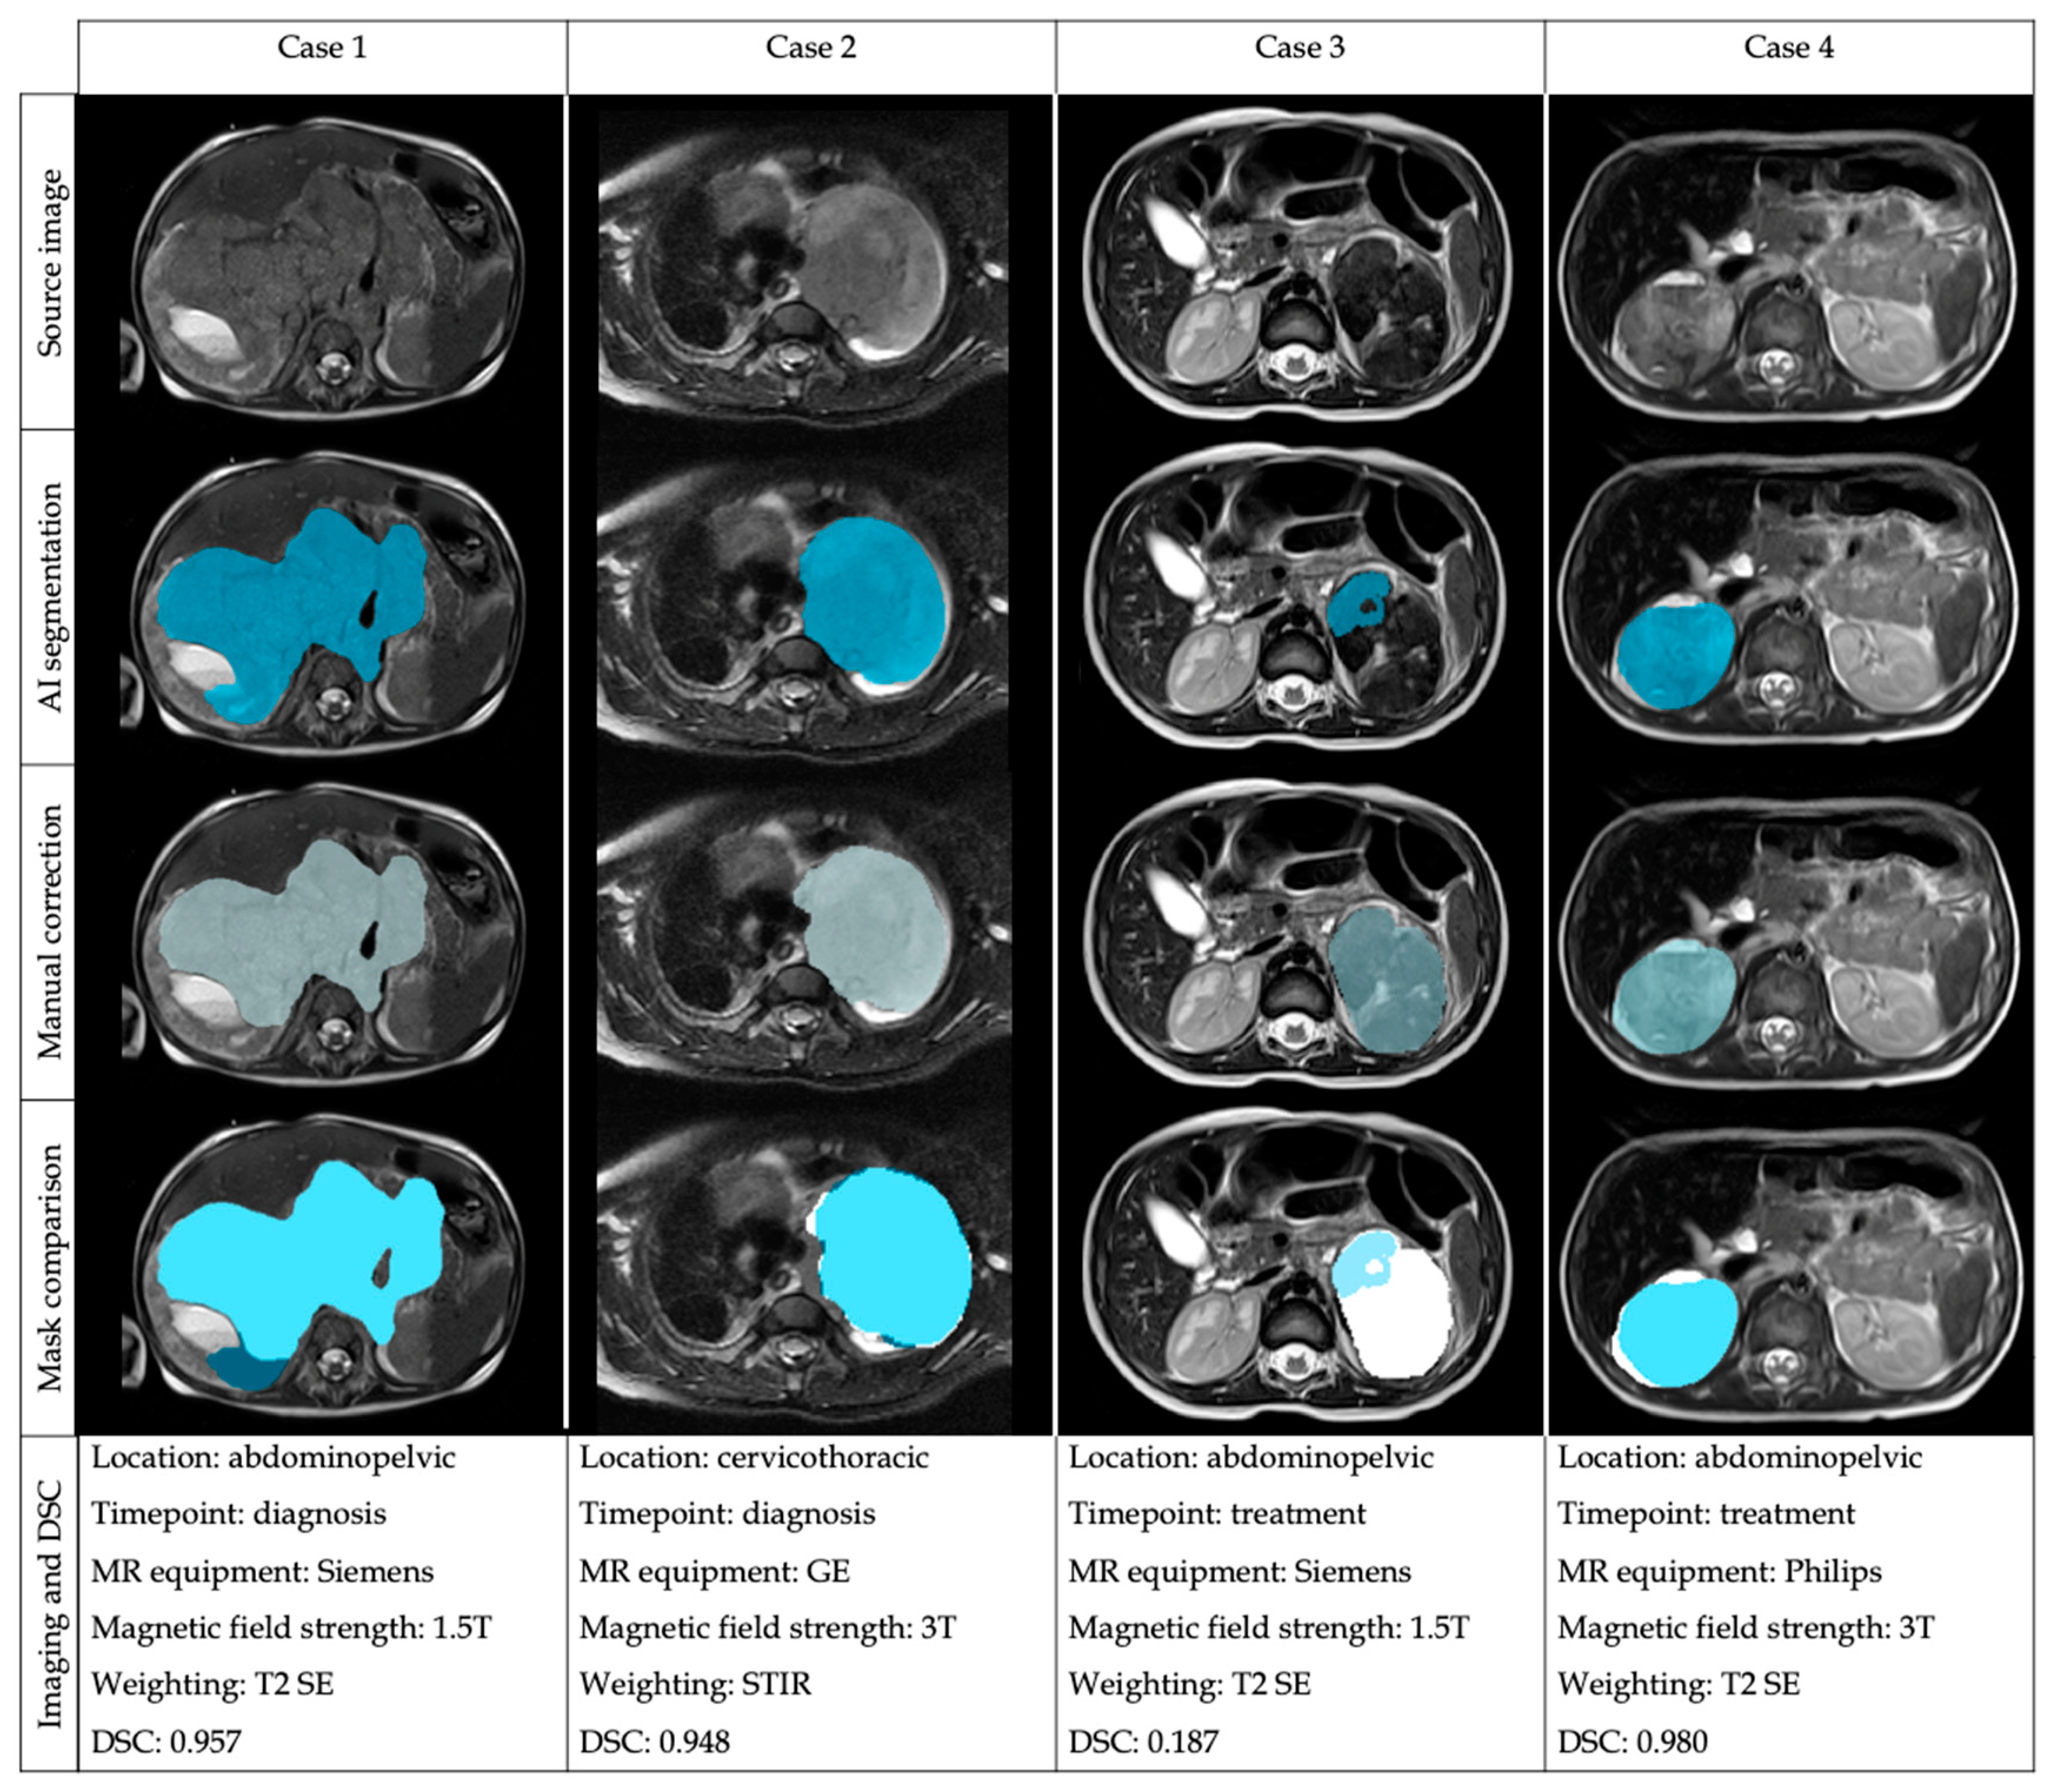

3.1. External Validation Results